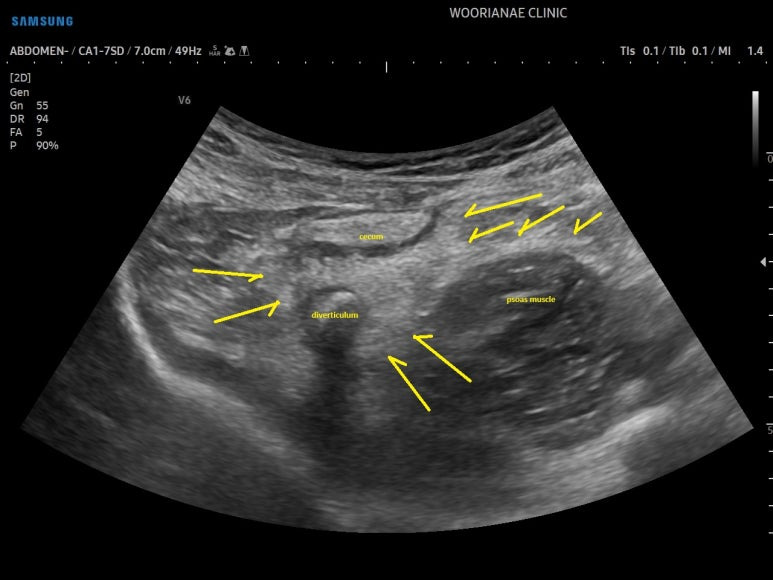

초음파 시행

회장 말단의 점막 비후가 의심되며

맹장 (cecum) 의 점막도 마찬가지 소견, 문제가 있는 것이다.

뚜렷한 게실의 확인

게실의 모습

대변과 공기층에 의해 후방감쇄가 있는 곳까지 게실의 길이는 더 있어 보인다.

컨벡스 프로브로 다시 조망해보면

게실 주변으로 염증성 지방변화가 장요근을 거의 타고 넘어가는 모습이다.